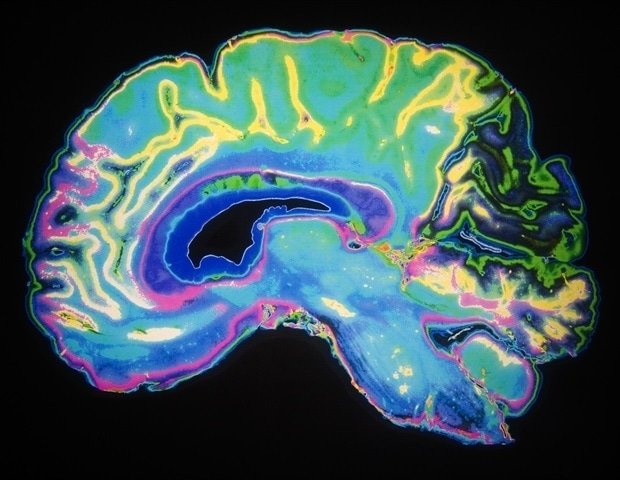

Clinicians use electroencephalography (EEG) to assess brain activity in epilepsy and sleep pathologies, but this powerful tool has shown promise in other conditions as well. Emerging evidence suggests that brain development, age, and time of day influence EEG signals measured during sleep. new e-neuro In this paper, researchers from the University Children’s Hospital Zurich investigated how differences in brain development, age, and sleep affect measurements of EEG signals recorded from awake people.

First, supporting previous findings, the researchers found that four measures of brain wave signals in 163 awake people aged 3 to 25 were affected differently by sleep history and age. Researchers say some measurements show an interaction between sleep history and age, which may reflect that children experience more brain changes during learning and memory than adults. This is a new discovery. Other measurements showed surprising developmental changes, with opposite results in children and adults after a single night’s sleep. These findings ultimately show that brain signals during wakefulness are dependent on previous sleep and that this influence differs in children and adults.

Because ADHD patients have developmental differences from neurotypical people, and because previous studies had identified differences in brain activity in EEG recordings taken from sleeping ADHD patients, the researchers further evaluated specific interventions using data from 58 awake children with ADHD. No differences in measurements were observed based solely on ADHD diagnosis, suggesting to the researchers that sleep quality, rather than symptoms of ADHD itself, may explain previously observed variation in EEG data, although further research is needed.

Snipes discusses how this initiative will improve brainwave research and clinical use. ”Although (researchers and clinicians) have been using this tool for some time, more sophisticated forms of data analysis could improve the interpretation of EEG recordings. Even if we know that certain variables change the EEG signal, we cannot infer what these changes mean unless we know which part of the signal is changing.”